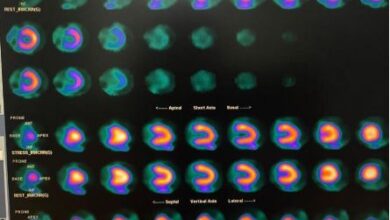

El diagnóstico oportuno impulsa mejores tasas de supervivencia en cáncer

Cleveland. La prevención y la realización periódica de chequeos médicos continúan siendo factores determinantes para reducir el impacto del cáncer a nivel mundial, destacó el doctor Alberto Pieretti, especialista de Cleveland Clinic, al señalar que los avances…